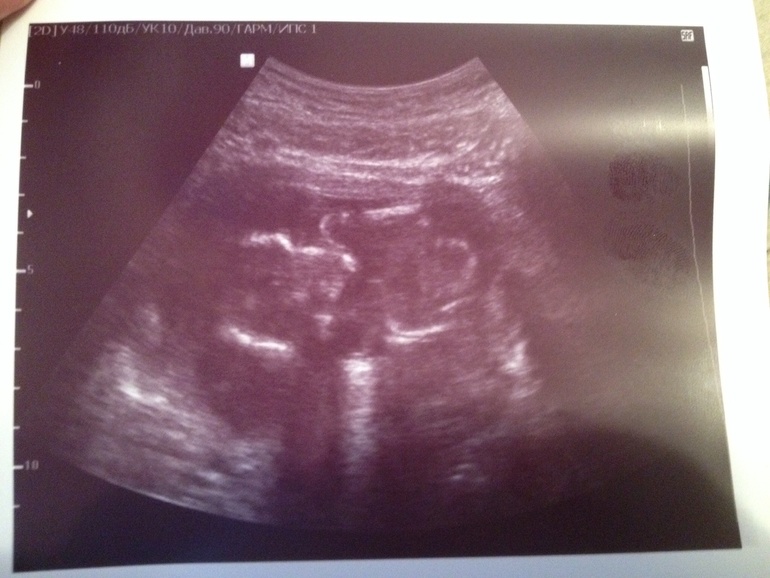

Алина 11 лет Доченька!!! Растем здоровые и длинные) Врач говорит, что родиться будущая модель) Мы очень ждем тебя, Маруся! Посмотрите еще 20 записей на эту тему Отменить Ответить Узи! Первые шевеления! Чаты Беременных Выберите чат: Январята-2026 Февралята-2026 Мартята-2026 Апрелята-2026 Майчата-2026 Июнята-2026 Июлята-2026 Августята-2026